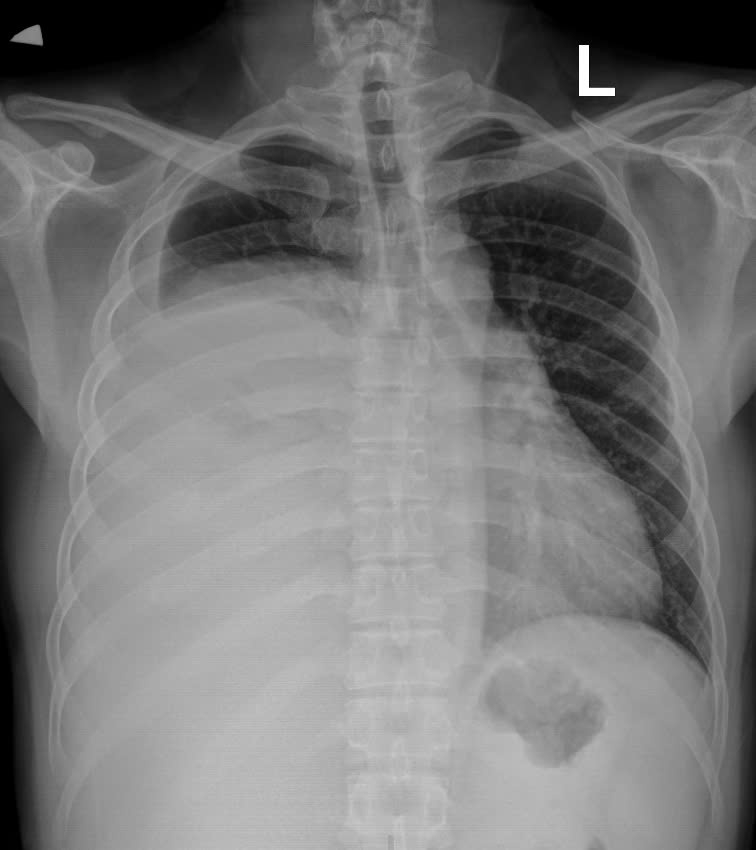

Hình ảnh phim chụp X.quang trước và sau khi phẫu thuật. Hình trước phẫu thuật (bên trái): Khối u xâm chiếm khoang ngực, gây xẹp gần như toàn bộ phổi phải

Qua thăm khám và chụp cắt lớp vi tính lồng ngực, các bác sĩ phát hiện khối u trung thất khổng lồ nằm lệch trong khoang màng phổi phải, chèn ép gây xẹp gần như toàn bộ phổi phải, đẩy lệch cơ hoành. Kết quả sinh thiết xác định đây là u bao sợi thần kinh Schwannoma – Một loại u lành tính hiếm gặp xuất phát từ bao thần kinh nhưng kích thước “khủng” hiếm thấy.

Khối u có kích thước 30×20 cm, nặng 3,6 kg, xâm chiếm gần như toàn bộ khoang ngực của bệnh nhân